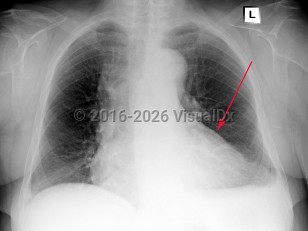

Pleuritic chest pain, Leg pain, Dyspnea, Developed acutely , History of Chronic obstructive pulmonary disease, History of Pulmonary hypertension, Tachycardia, Unilateral leg edema, Sinus tachycardia, S1Q3T3 pattern, T wave inversion, Pathologic Q waves, 70-79 year old Female

Pulmonary embolismPulmonary embolism

Pneumothorax